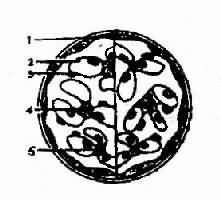

2.局灶性肾小球肾炎和肾局灶性硬化,病变仅限于双侧肾脏的一部份肾小球,而这部分肾小球的病变也仅位于毛细血管袢的个别节段(图4-2-3),偶而波及一个完整的肾小球,病变性质因病变和病程的不同,可表现为灶状系膜细胞和系膜基质增生(局灶性增殖性肾小球肾炎),也可表现为灶状毛细血管袢的纤维素样坏死(局灶性坏死怀肾小球肾炎),还可表现为灶状的纤维组织增生(局灶性硬化性肾小球肾炎)。电镜观察除上述变化外,尚可见毛细血管基膜或系膜区有电子致密物沉积。荧光检查依病因不同在病变部位的肾小球毛细血管基膜或系膜区可能有IgA、IgG、Igm 以及纤维蛋白抗原沉积。

图4-2-3左侧为正常肾小球模式图,右侧为局灶性增殖性肾小球肾炎,部分系膜区系膜细胞和基质增生

1、肾小囊壁层2、基膜3、上皮细胞 4.内皮细胞 5、系膜细胞及基质